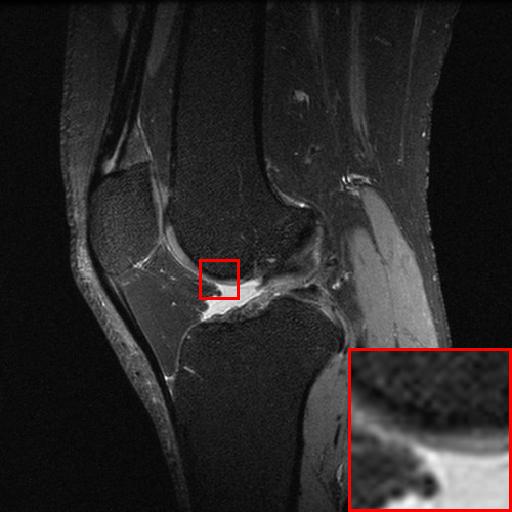

Figure 6: Reconstruction results of each algorithm for low-doze chest CT images.

III-D Super-resolution Reconstruction of Low-dose CT images

Medical pictures, such as computed tomography (CT) scans, are widely used in clinical applications such as noninvasive illness detection, anatomical imaging, and treatment planning, all of which need judgment while doing CT scans. These imaging approaches, however, have some drawbacks. During CT scans, for example, radiation damage is unavoidable. Low-dose CT (LDCT) is currently the clinically recommended strategy for preventing irreversible radiation harm to the body, however it comes at the cost of getting CT pictures with low resolution or noise contamination. The spatial resolution is generally coarser than that of CT imaging in order to get images with a high signal-to-noise ratio. As a result, obtaining high-resolution scanned images with a low-dose CT scanner is now a challenge.

In this section, we selected chest CT images of COVID-19 patients in an actual hospital [26] for our experiments. The visualization results of the experiments are shown in Figure 5 and Figure 6. The experimental results show that our proposed T-GAN is also applicable to the super-resolution reconstruction of low-dose CT images, and the high-resolution images obtained by our model have more detailed information compared with the baseline algorithm.